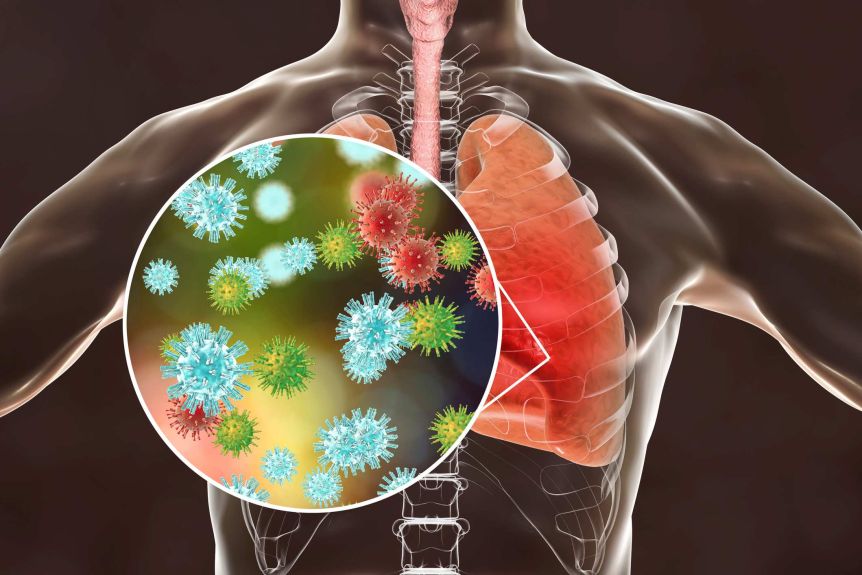

ଜୁରିଚ୍,୨୩।୪: କରୋନା ଭାଇରସ କେବଳ ଫୁସ୍ପୁସ୍କୁ ନୁହେଁ ରକ୍ତ ମାଧ୍ୟମରେ ଖୁବ୍ଶୀଘ୍ର ଅନ୍ୟ ଅଙ୍ଗକୁ ମଧ୍ୟ ସଂକ୍ରମଣ କରିପାରେ ବୋଲି ବିଶେଷଜ୍ଞମାନେ କହୁଛନ୍ତି। ସ୍ବିଜରଲାଣ୍ଡର ଜୁରିଚ୍ ବିଶ୍ୱବିଦ୍ୟାଳୟର ଗବେଷକମାନେ ଏହି ମତ ଦେଇଛନ୍ତି। କରୋନା ଭାଇରସ ଶରୀରର ଯେ କୌଣସି ଅଙ୍ଗରେ ରକ୍ତ ପହଞ୍ଚାଉଥିବା ରକ୍ତବାହୀ ଉପରେ ସିଧାସଳଖ ଆକ୍ରମଣ କରିପାରେ ବୋଲି କୁହାଯାଉଛି। ଫଳରେ ଏହା ଶରୀରର ଯେ କୌଣସି ଅଙ୍ଗକୁ କ୍ଷତି ପହଞ୍ଚାଇପାରେ ଏବଂ ଏହା ଉଚ୍ଚ ରକ୍ତଚାପ, ଡାଇବେଟିସ, ମେଦବହୁଳତା, ହୃଦ୍ରୋଗ ଥିବା ବ୍ୟକ୍ତିଙ୍କ ପାଇଁ ବିପଦ ସୃଷ୍ଟି କରିପାରେ। କରୋନା ସଂକ୍ରମିତ ବ୍ୟକ୍ତିଙ୍କ ରକ୍ତବାହୀକୁ ଦେଖିବା ପରେ ଏହା କ୍ଷତିଗ୍ରସ୍ତ ଥିବା ଜଣାପଡିଛି। ଏହାର କାରଣ ହେଉଛି ACE2 ରିସେପ୍ଟର ଏନଜାଇମ। ଏହି ଏନଜାଇମ ଫୁସଫୁସ, ଧମନୀ, କିଡ୍ନୀ ଓ ହୃତପିଣ୍ଡରେ ମିଳିଥିବାରୁ ଏହା ଖୁବ୍ଶୀଘ୍ର ସଂକ୍ରମିତ ହୁଏ ବୋଲି କୁହାଯାଉଛି। ଅଟୋପ୍ସସି ରିପୋର୍ଟ କହିଛି ପ୍ରଥମରୁ ଯେଉଁମାନେ ଉଚ୍ଚ ରକ୍ତଚାପ, ଡାଇବେଟିସ, ମେଦବହୁଳତା, ହୃଦ୍ରୋଗରେ ପୀଡିତ ଥିବେ ସେମାନଙ୍କ ରକ୍ତବାହୀ ଦୁର୍ବଳ ଥିବାରୁ ସେମାନଙ୍କ ନିକଟରେ କରୋନା ସହଜରେ ସଂକ୍ରମିତ ହୋଇଥାଏ।